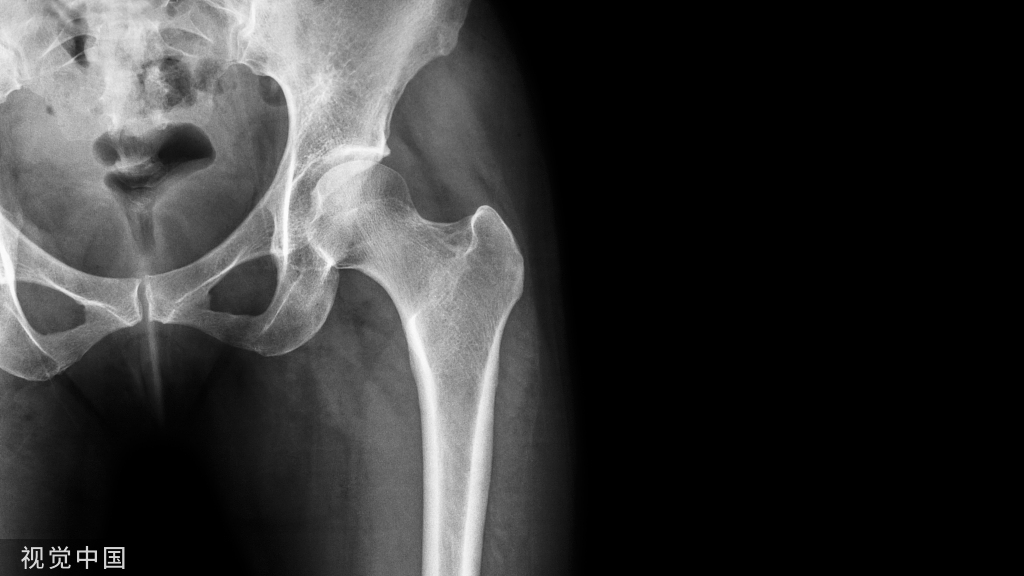

病例1:

病例2:

尽管文献报道描述该手术技巧比较有优势,但是实际操作过程中可能存在以下问题,供大家参考:

1. 关于皮肤切口的问题。文献典型病例图中采用腓骨外侧切口,如后踝采用钢板固定,该切口可能置钉较为困难;

2. 关节面显露问题。该手术技巧的适应症和腓骨骨折线走形有很大关系,较高的腓骨骨折线撑开后无法评估关节面是否匹配,只能清理断端小骨块,难以评估关节面复位程度;3. 后踝与外踝固定顺序问题。在腓骨撑开情况下,由于下胫腓韧带的牵拉,要复位固定后踝其实是存着较大的软组织张力的,如何保证腓骨撑开情况下固定后踝,可能实际操作上有难度。